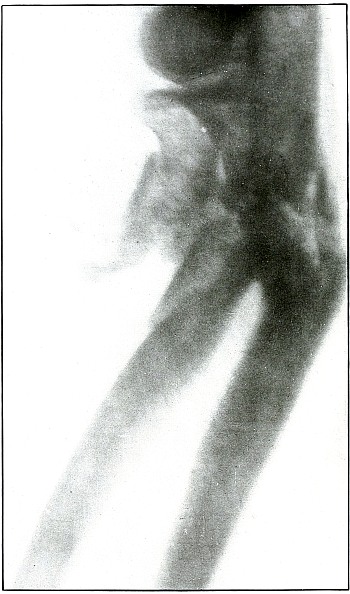

| 47. |

Gunshot wound, gluteal region |

104 |

| 48. |

Gunshot wound, thigh |

106 |

| 49. |

Gunshot wound, thigh |

108 |

| 50. |

Gunshot wound, thigh |

110 |

| 51. |

Gunshot wound, thigh |

112 |

| 52. |

Gunshot fracture, femur |

114 |

| 53. |

Gunshot fracture, femur |

116 |

| 54. |

Gunshot fracture, femur |

118 |

| 55. |

Gunshot fracture, femur |

120 |

| 56. |

Gunshot fracture, femur |

122 |

| 57. |

Gunshot fracture, femur |

124 |

| 58. |

Gunshot fracture, femur |

126 |

LOWER EXTREMITY.

Plate 47.

[Pg 105]

Rifle—Plate 47.

LOWER EXTREMITY.

Gunshot Wound of the Gluteal Region,

with Lodgment of the Bullet Near the Ischium.

Wound of entrance, over gluteal prominence on a transverse line

through the great trochanter.

Wound of exit, none.

There was no bone injury in this case. The bullet, to have lodged in

the soft parts after relatively slight penetration, must have struck

the body at extreme range when its energy was almost spent in flight,

for its normal outline indicates that it was not retarded by ricochet.

The long axis is almost perpendicular to the plate. As the posterior

pelvis was next to the plate, the fairly dense shadow shows the

projectile was not far from the plate and behind the ischium.

The treatment is conservative; infection in such cases is extremely

rare; and only pain or impaired function after many months of

convalescence justifies operation for removal of the missile.

[Pg 106]

Plate 48.

[Pg 107]

Rifle—Plate 48.

LOWER EXTREMITY.

Gunshot Wound of the Thigh,

with Lodgment of the Bullet.

Wound of entrance, outer aspect of the thigh at the junction of the

upper and middle thirds.

The slight penetration without bone injury and with slight deformity

of the nose of the bullet indicates that the wound was caused by a

ricochet shot at extreme range, after its energy was almost spent.

With the posterior aspect of the thigh next to the plate, the dense

shadow and the nearly normal size of its outline indicate that the

bullet was in the same relative position and that it lay posterior to

the neck of the femur.

As such wounds are rarely infected, the treatment is conservative,

and a search for the missile is only justified by serious infection,

pain, or impaired function.

[Pg 108]

Plate 49.

[Pg 109]

Rifle—Plate 49.

LOWER EXTREMITY.

Gunshot Wound of the Right Thigh,

with Lodgment of the Bullet Behind the Femur.

There is no injury of the bone in this case, as the bullet lodged in

the muscles posterior to the lower third of the femur without striking

the bone. The lighter circular area of the larger end of the shadow

of the projectile shows that its base is farther from the plate than

its nose, which was probably flattened and bent by the ricochet which

reduced its velocity so as to give it but slight power of penetration.

It is not easy to determine from inspection of the plate which side of

the leg lay next to the plate.

With a history of the wound of the right thigh and with the outside

of the leg next to the plate, the projectile must have lain near the

plate on the outside behind the lower end of the femur, midway between

the skin and bone.

The markings seen on the bone are not concerned with the wound, as the

same effect in the plate is seen in the areas beside the bone.

The treatment is conservative; infection is rare.

[Pg 110]

Plate 50.

[Pg 111]

Rifle—Plate 50.

LOWER EXTREMITY.

Gunshot Wound of the Right Thigh,

with Lodgment of the Bullet Behind the Femur.

There is no injury to the bone. The large diameter, shortened length,

and slight density of the shadow show the bullet to be some distance

from and inclining toward the plate and lodged in the muscles behind

the femur, nearer the side away from the photographic plate. It is

difficult to identify the right or left thigh from the radiograph, but

with the history of the wound in the right thigh and the outside of

the leg next to the plate the ball would lie nearer the inside than

the outside of the thigh, nearer the surface behind the femur. As the

shadow shows irregular outline and the location of the bullet low

velocity, the wound was caused by a ricochet shot at very long range.

The treatment is expectant and the course naturally favorable.

[Pg 112]

Plate 51.

[Pg 113]

Rifle—Plate 51.

LOWER EXTREMITY.

Gunshot Wound of the Thigh,

with Lodgment of the Missile.

As there is no injury to the bone, the bullet is not deformed. Its

penetrating power was not great enough to carry it through the tissue

so it must have struck the leg at extreme range when its energy was

almost spent.

The actual length of the bullet is 1.25 inches; the length of the

shadow is about 1.50 inches.

The increased length and the relatively slight density of the shadow

indicate the bullet to be some distance from the plate. The case

history places the wound in the right thigh, and the posterior surface

of the leg lay next to the photographic plate. As the density of the

shadow is not greater than the thickest portion of the bone, the

bullet probably lies in front of the border of the outer tuberosity of

the femur.

Although the surgeon’s diagnosis had to be made from the only

available plate, there is something of a speculative element in these

deductions, because if the reaction in the knee joint prevented the

patient from extending the leg the increased length of the bullet

shadow could be accounted for by this position, which would permit the

bullet to lie behind the bone and yet far enough from the plate to

account for the shadow enlargement. The nose of the bullet is at

the epiphyseal line, which is shown in the femur.

[Pg 114]

Plate 52.

[Pg 115]

Rifle—Plate 52.

LOWER EXTREMITY.

Gunshot Fracture of the Upper Shaft of the Femur.

The course of the bullet was anteroposterior and pierced the axis

of the shaft of the femur with three radiating lines of fracture,

resulting from the perforating action of the bullet striking the bone

at long range and with greatly reduced energy.

This plate shows the lateral separation of large fragments,

which is typical of gunshot wounds of long range.

Such wounds are usually not infected.

Emergency treatment is antiseptic dressing and coaptation with

extension and temporary splint, so that it may support the bone for

transportation and may be easily removable at place of continued

treatment.

In these cases with lateral separation of fragments, it is imperative

to supplement extension with pressure in a line perpendicular to the

long axis of the femur.

[Pg 116]